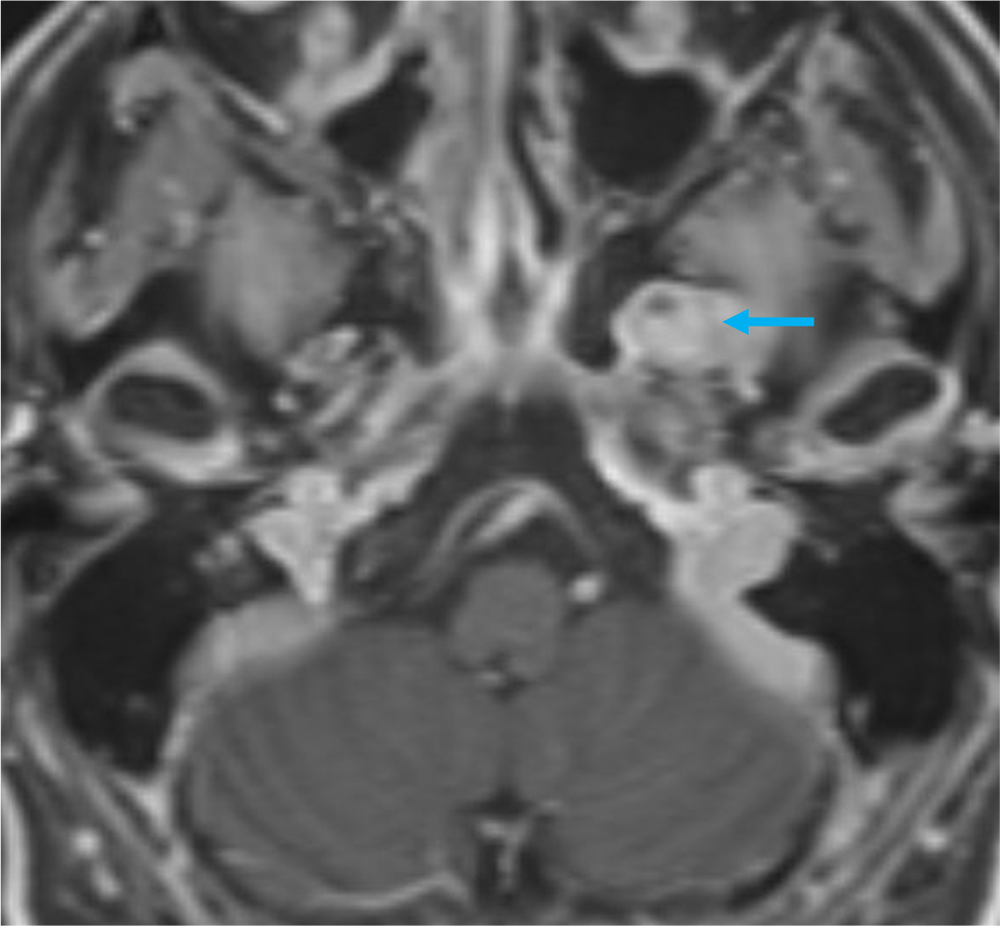

単純MRIのT2強調画像では左メッケル腔から背側に突出する腫瘍を認め、三叉神経鞘腫と髄膜腫が鑑別となる。Gd造影剤の脂肪抑制T1強調画像では腫瘍は全体に濃染し、冠状断では卵円孔を介した頭蓋外進展が見られ、三叉神経鞘腫の可能性が高い。内側では海綿静脈洞を圧排、背側では橋の軽度圧排も見られる。有症状であり、手術が施行され、三叉神経鞘腫と診断された。

三叉神経鞘腫を確実に診断するためには、神経走行に沿った進展を確認することである。Gd造影剤を用いた3Dの脂肪抑制T1強調画像を撮影することで、thin sliceの造影CTと同様に後から再構成したMPRを作成するにより、腫瘍の進展方向を確実に診断することが可能であり、本症例には必須のシーケンスと思われた。